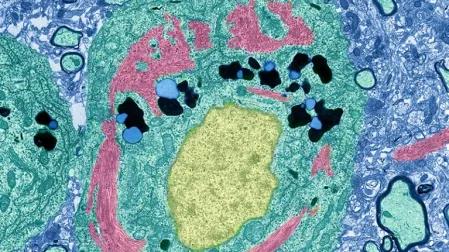

En entrevista con la revista Nature, la neurocientífica Li-Huei Tsai del Instituto Tecnológico de Massachusetts (MIT) en Cambridge y sus colegas. APOE4 activa las células cerebrales productoras de aislamiento conocidas como oligodendrocitos para acumular la molécula grasa colesterol, un tipo de lípido, en todos los lugares equivocados.

Esto interfiere con la capacidad de las células para cubrir las fibras nerviosas con una envoltura protectora hecha de un material rico en lípidos llamado mielina. La señalización eléctrica en el cerebro luego se ralentiza y la cognición generalmente sufre.

El equipo de Tsai había relacionado previamente los cambios de lípidos con el mal funcionamiento de otros tipos de células, incluidas algunas que ofrecen apoyo estructural a las neuronas 2 y otras que brindan protección inmunológica al cerebro 3 . Los últimos hallazgos agregan oligodendrocitos y su función esencial de mielina a la mezcla.

El equipo creó cultivos de oligodendrocitos humanos con varias formas del gen APOE . El grupo descubrió que las células con la variante APOE4 tendían a acumular colesterol dentro de los orgánulos internos. Expulsaron cantidades relativamente bajas de colesterol, lo que los hizo menos hábiles para formar vainas de mielina.